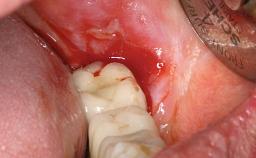

Surgical treatment of a 68-year-old female patient who experienced failure of her conventional bridge in the right maxilla. After removal of the compromised abutment teeth and a healing period of 6 weeks, a sinus floor elevation procedure using the lateral window technique and a composite graft to correct the insufficient bone height is carried out.

Two dental implants are placed in the same surgical session. The case concludes with the presentation of the final fixed dental prosthesis with a distal cantilever unit.